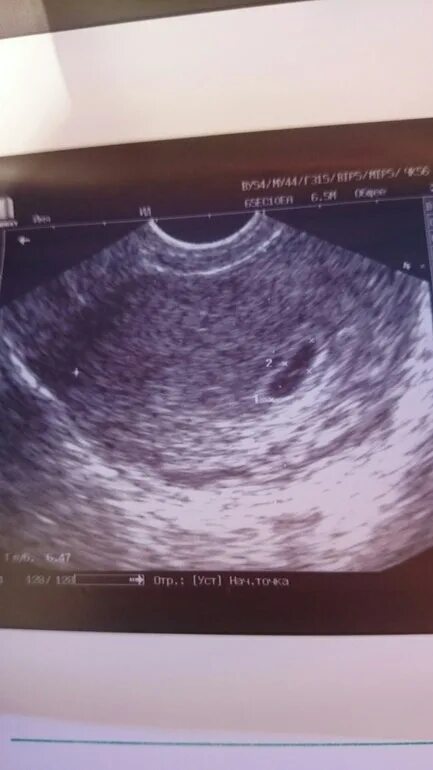

Плодное яйцо 4 5 мм